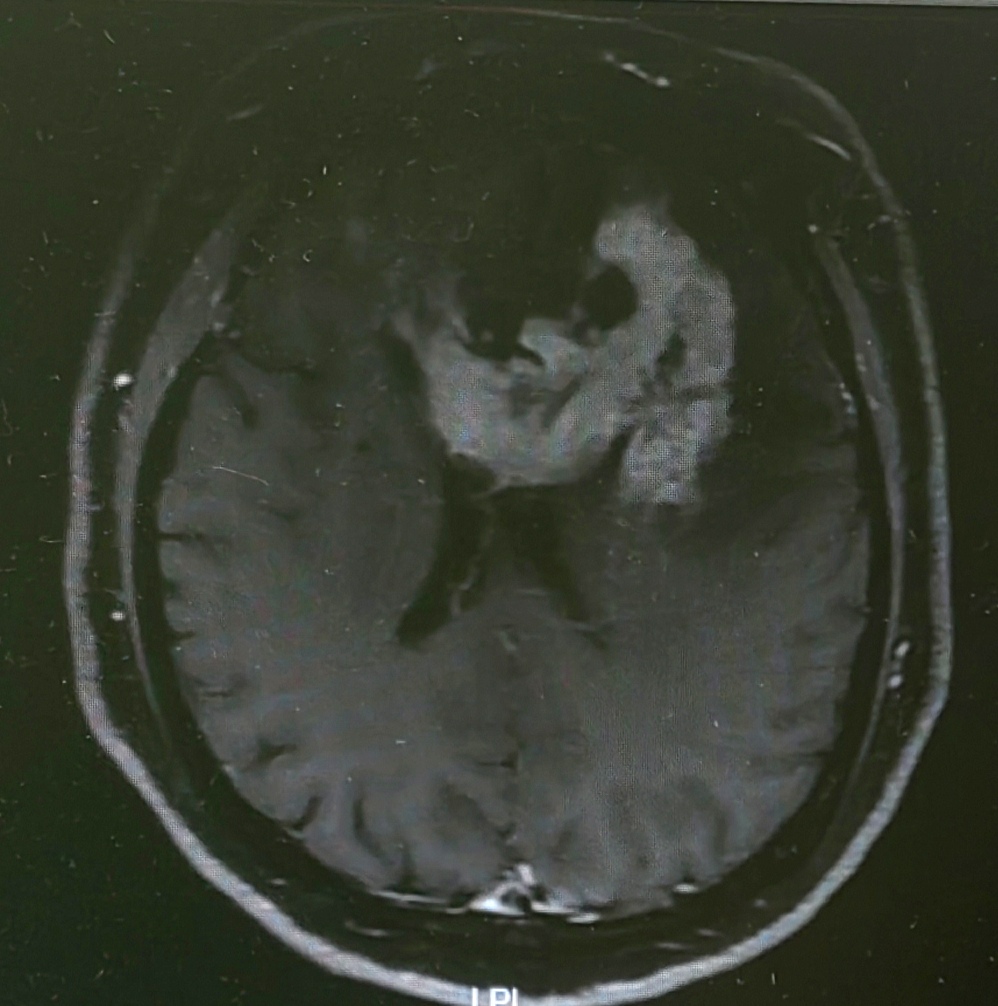

增强MRI呈跨胼胝体团块样强化灶